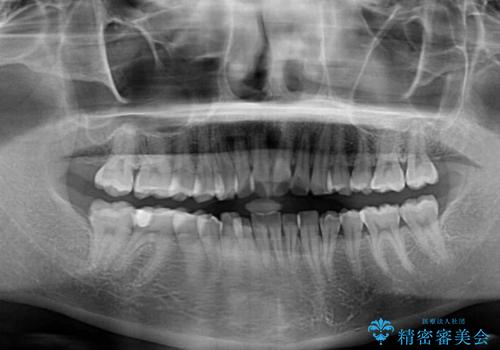

前歯のデコボコをインビザラインできれいに整える

- 前歯のデコボコと上下の隙間を気にして来院された患者様です。

前歯の捻れを改善するとともに、口元が少しでも引っ込むように治療計画を立て、仕上げることができました。